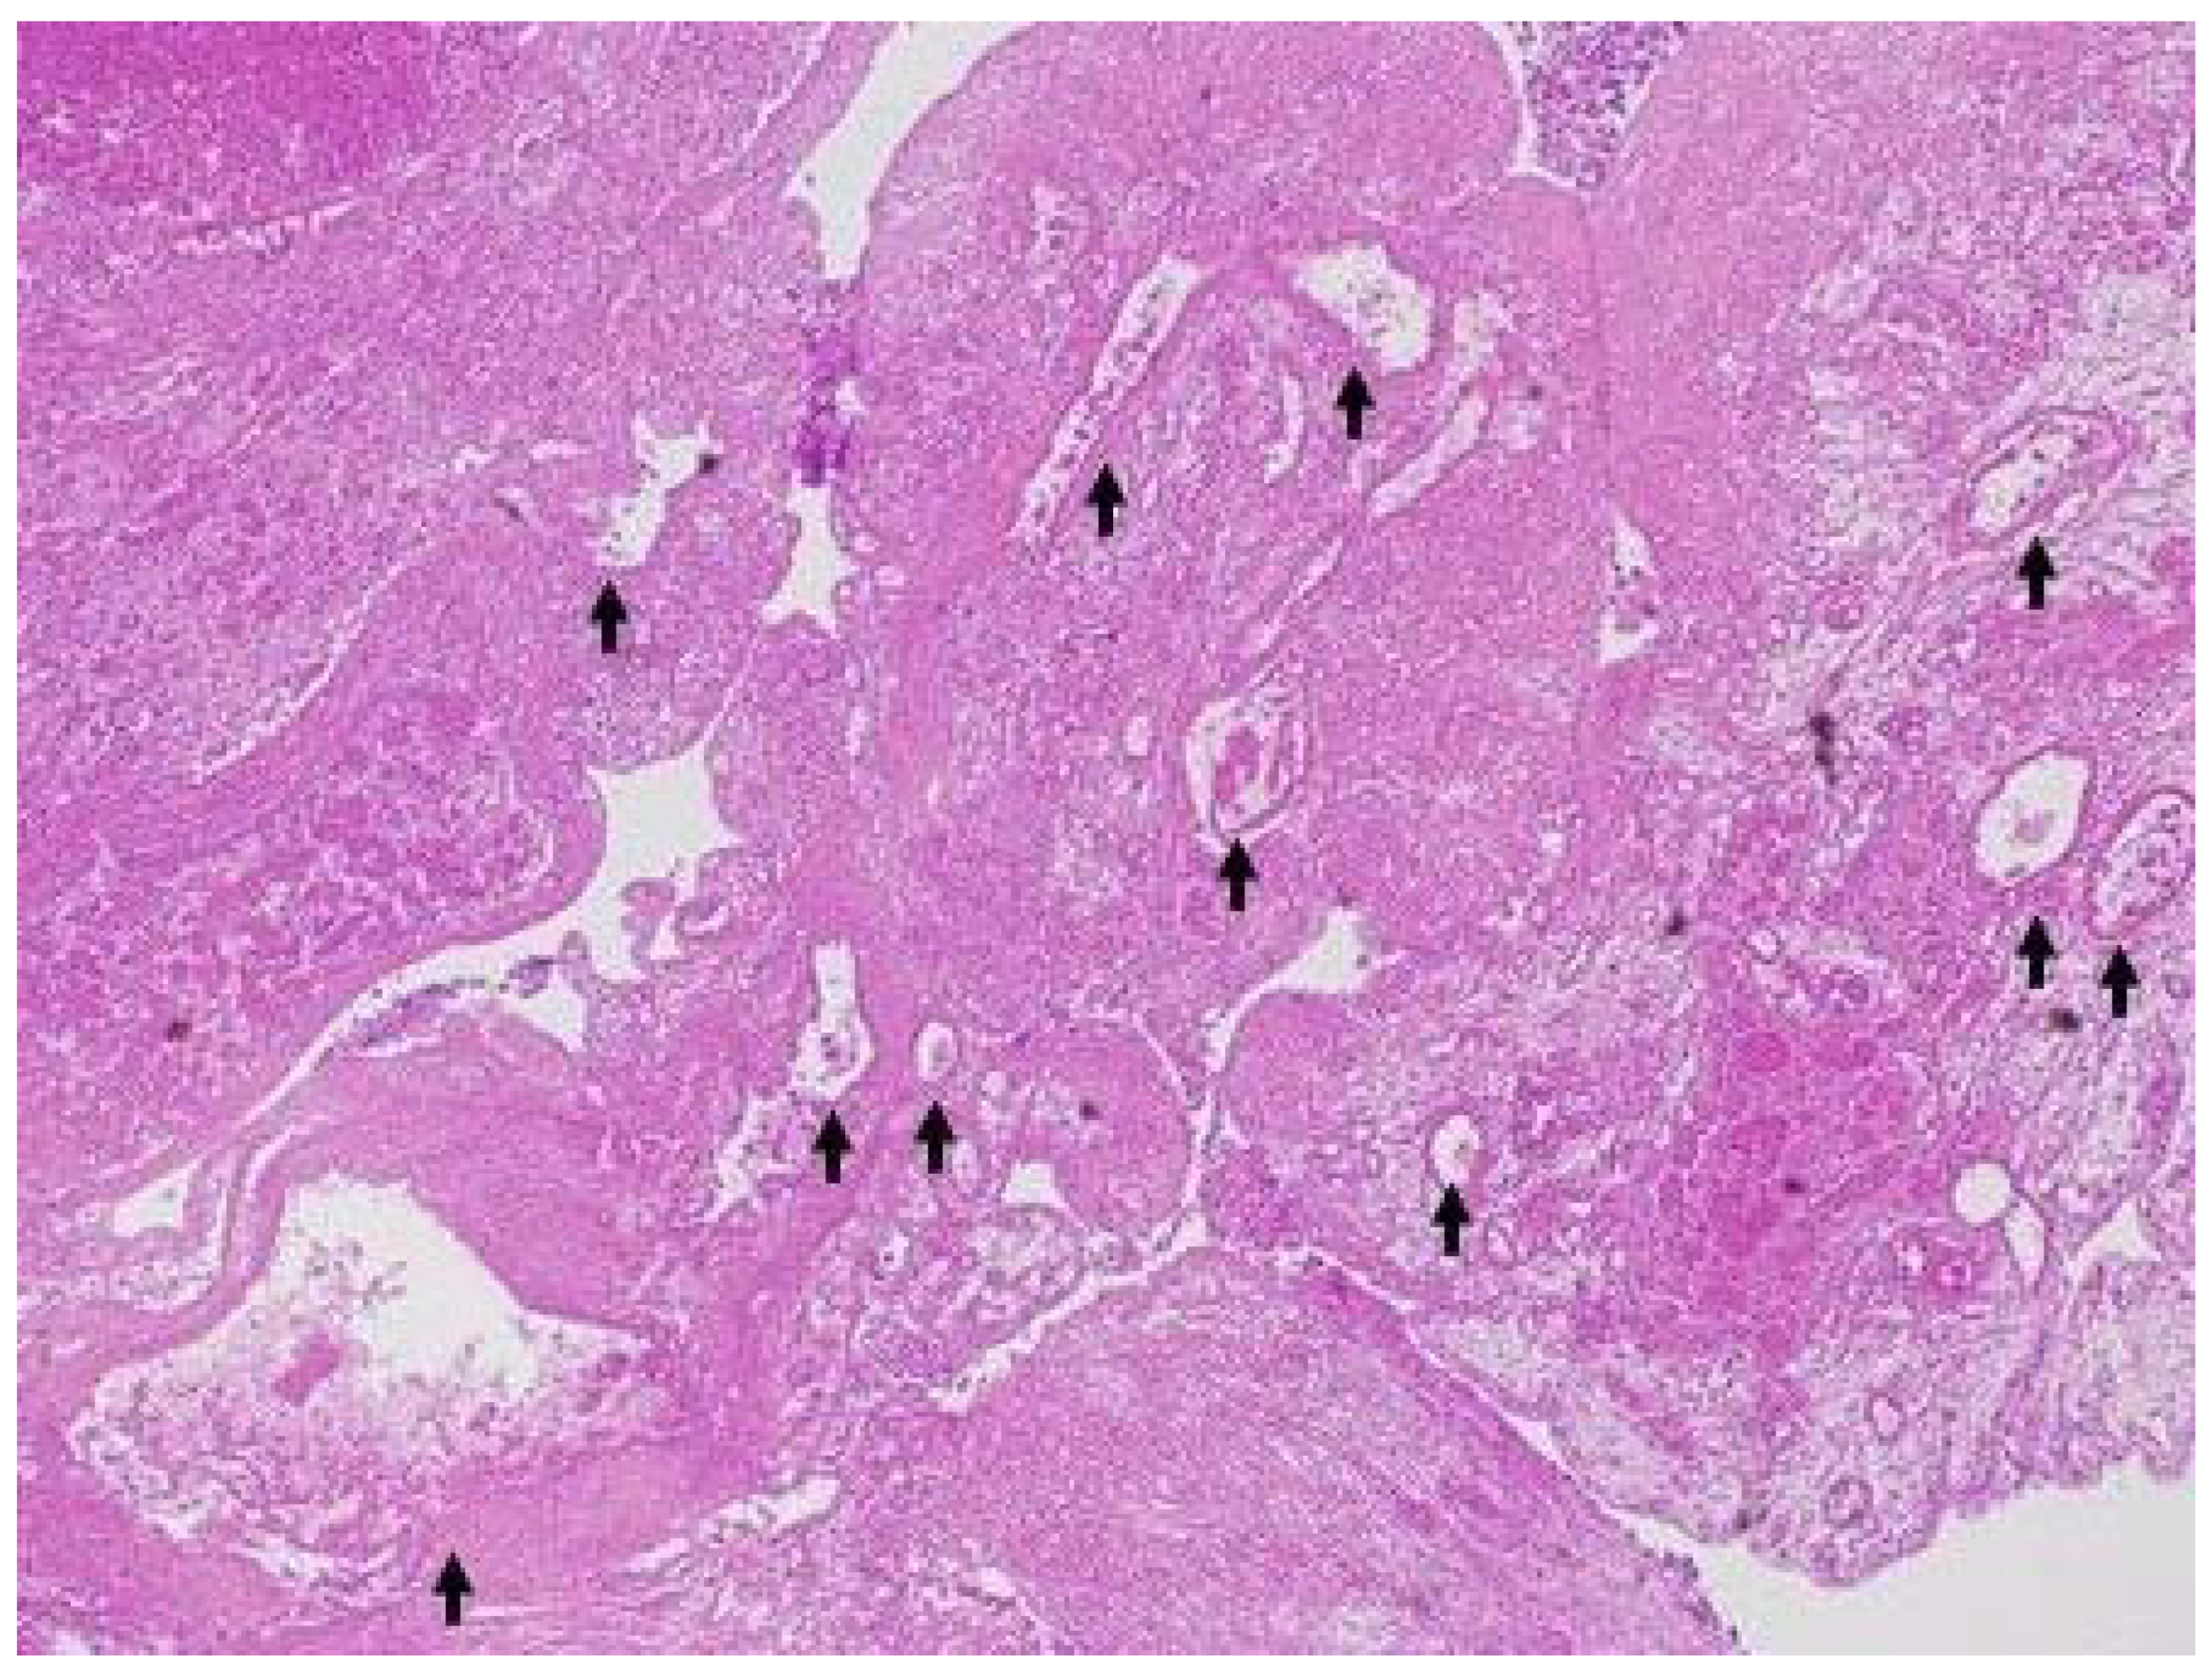

2.4. DFI-EUS

| DFI-EUS finding | ||

| Regular vessel | 3 (100%) | 1 (11%) |

| Irregular vessel | 0 (0%) | 8 (89%) |